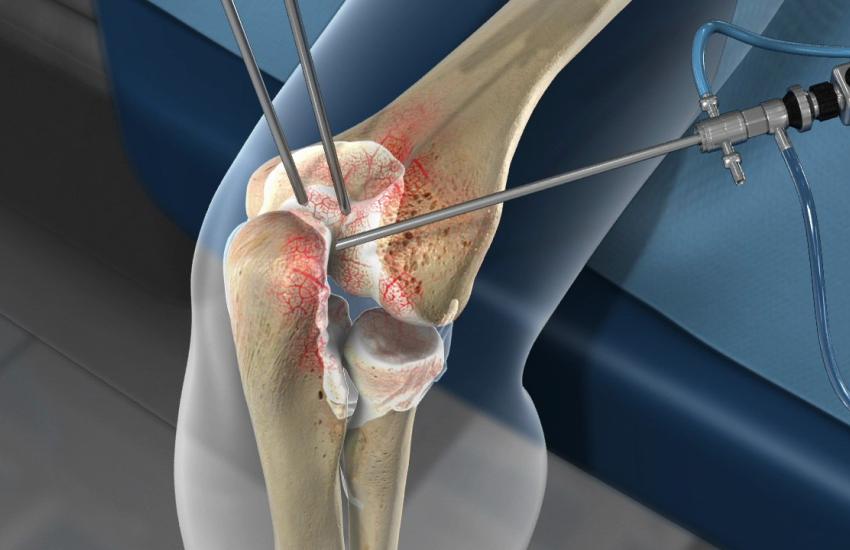

Симуляційний тренінг «Оволодіння практичними навичками артроскопії колінного суглобу»

Мета заходу: Удосконалення теоретичних та практичних знань, опанування та відпрацювання базових навичок виконання самостійної діагностичної артроскопії колінного суглоба, а також певного обсягу реконструктивних втручань.

Перелік компетентностей, що набуваються або вдосконалюються - навички з установки порталів, артроскопічна анатомія та діагностична артроскопія колінного суглобу, видалення вільних тіл, синовектомія, техніки відновлення розривів меніску: all – inside, inside out, outside–in, техніки операцій з відновлення ПХЗ. Переваги та недоліки, резекція та відновлення розривів менісків, забір трансплантату, відновлення ПХЗ.

Курс містить навчальні матеріали та інтерактивні вправи (дискусії), відпрацювання практичних навичок в операційній, які допоможуть Вам набути знань та застосовувати їх в роботі.